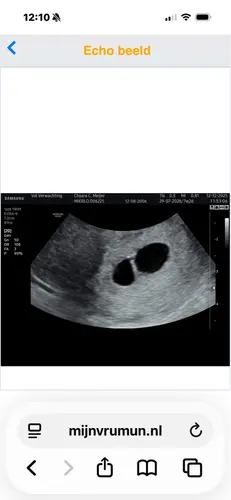

Ik heb geen tweeling of met 5 weken gedaan ik heb een echo gehad met 5 weken en 6 dagen en daar zag je al wel wat op en een kloppend hartje maar goed ik was toen 6 dagen verder dan jij nu bent en voor zo鈥檔 prille zwangerschap zijn 6 dagen veel!

Dit was mijn echo foto met 5 weken en 6 dagen .